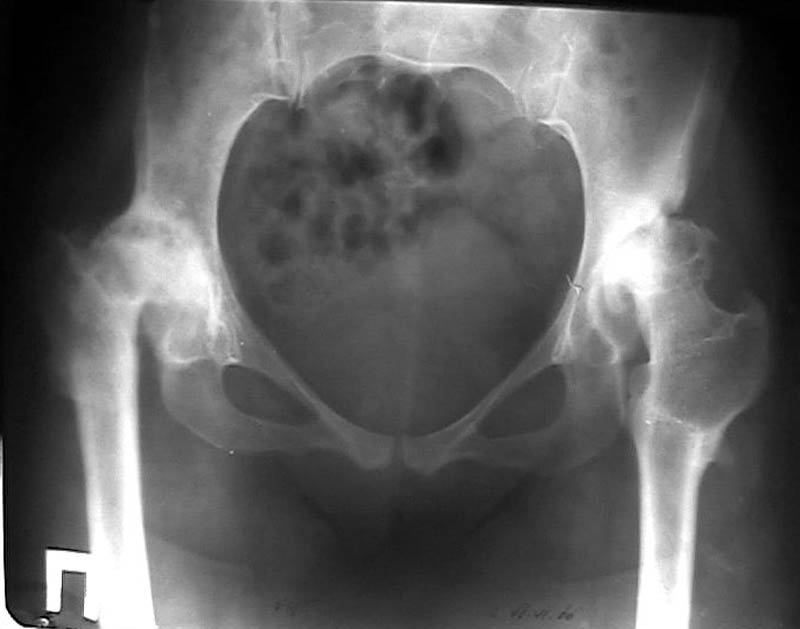

Мужчина, 38 лет. Двусторонний диспластический коксартрз, кифосколиоз.Правый сустав прооперирован 12.12.00, левый - в апреле 2003 г. Справа вывихнулась <чашка>.

Предполагается заменить <чашку>, наростив крышу <тутопластом>? Возможно ли использовать бесцементную <чашку>? Мнения? Заранее благодарю! С уважением,А.В.Владзимирский